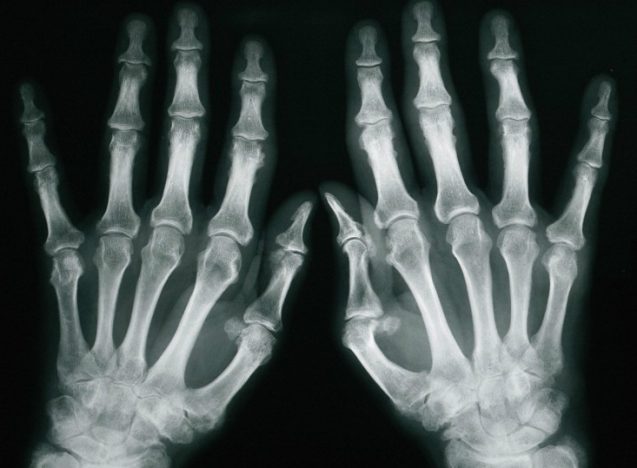

דלקות פרקים, נעים להכיר?

דלקת פרקים היא למעשה שם כולל למספר מחלות אשר באות לידי ביטוי בתסמינים שונים בפרקי הגוף. קבוצת מחלות זו יכולות להיות זיהומיות, דלקתיות או ניווניות. התסמינים של דלקת פרקים: כאבים במפרקים כאשר מדובר מצב דלקתי חום מקומי, אודם והגבלה בתנועה. כאשר מדובר במצב זיהומי עלול להופיע עלייה בחום הגוף. קשיחות במפרקים ירידה בטווח התנועה סוגים נפוצים של דלקות פרקים: יש מגוון רחב של סוגי דלקות פרקים, השוני בניהם נובע במספר המפרקים המעורבים, כאשר ישנה חלוקה לשתי קבוצות עיקריות: הראשונה, כאשר מעורב מפרק אחד (מונוארצריטיס) והשנייה כאשר מספר מפרקים במקביל (פוליארתריטיס). דלקת מפרקים שגרונית – דלקת זו משתייכת לקבוצה השנייה משום…